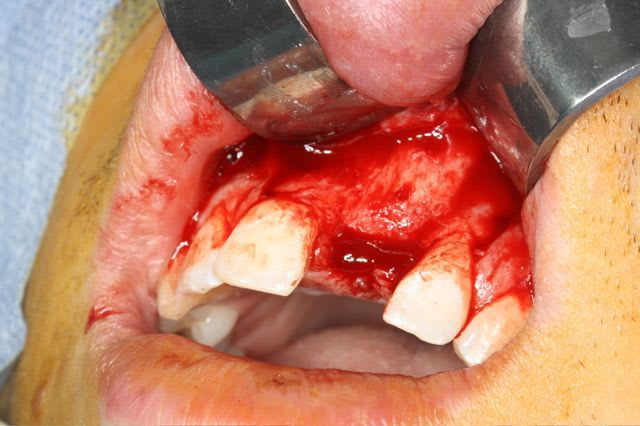

Pour le fun ! car pas bcp de photos en ce moment sur nonol

la dent était absente depuis 8 ans suite à "accident" de la vie (à 5h du mat'...)

très classiquement:

greffe onaly,

dépose des vis et pose de l'implant à 5mois1/2 avec un cj roulé et mise en place de la vis de cica,

et 3 mois 1/2 après empreinte

15j après essayage pilier et biscuit, visite au labo pour "finition en bouche" et 3 h après scellement.

en temporisation, la vieille PAP du patient (raison €€€ )

pour la greffe: un lit de copeaux généreux et un bloc corticale par dessus et des copeaux pour boucher les espaces. Pas de membrane par dessus, seulement le périoste.